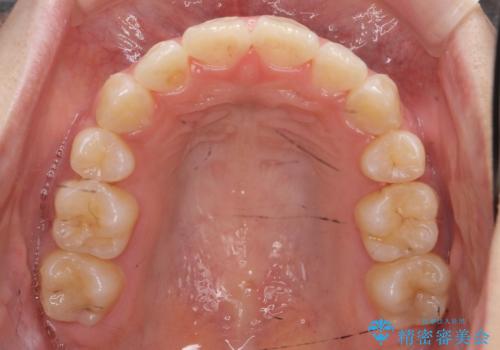

八重歯の治療 仕上がり重視で

- 八重歯を主訴に来院。

仕上がり重視とのことで、小臼歯を抜歯し、スタンダードな治療方法で仕上げています。

上下の小臼歯を抜歯しています。

矯正用インプラントアンカーを使用してしっかり前歯を下げたため、口元が大きく改善しています。